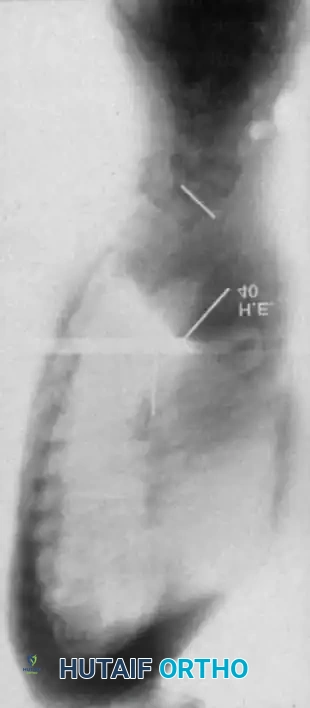

Curves with significant sagittal plane deformity are highly prevalent in dystrophic scoliosis. Neurofibromatosis kyphoscoliosis is particularly notorious, characterized by acute, rigid angulation in the sagittal plane and striking destruction or deformity of the vertebral bodies near the apex. Severe thoracic lordoscoliosis has also been documented by Winter, presenting unique respiratory and biomechanical challenges.

Dystrophic Kyphoscoliosis

Dystrophic scoliosis coupled with angular kyphosis represents one of the most formidable challenges in spine surgery. Patients with this pathology respond exceptionally poorly to posterior fusion alone. Consistent, long-term success is achieved almost exclusively through combined anterior and posterior (360-degree) fusions.

Winter and Hsu emphasized that the primary reasons for failure in these curves are inadequate bone graft volume and insufficient fusion area. The surgical strategy must include:

1. Anterior Release and Corpectomy: The entire structural area of the deformity must be addressed anteriorly. This requires complete, aggressive disc excision back to the posterior longitudinal ligament.

2. Structural Strut Grafting: Strong strut grafts are biomechanically imperative to support the anterior column and prevent kyphotic collapse. Fibular allografts or autografts, supplemented with rib and iliac crest cancellous bone, are standard.

3. Vascularized Rib Grafts: For severe, rigid kyphoscoliotic deformities, vascularized rib graft augmentation (as described by Bradford) provides superior biological healing potential in the hostile, dysplastic environment of the NF-1 spine.

4. Posterior Instrumentation: Following the anterior stage, robust posterior segmental instrumentation and arthrodesis are performed.

For smaller dystrophic kyphoscoliosis (kyphosis <40 degrees), posterior instrumentation and arthrodesis may be attempted early, but the fusion mass must be explored at 6 to 12 months. If kyphosis exceeds 50 degrees, the combined anterior/posterior approach is non-negotiable. The anterior fusion must extend one or two levels beyond the end vertebrae of the kyphotic segment to prevent junctional failure.